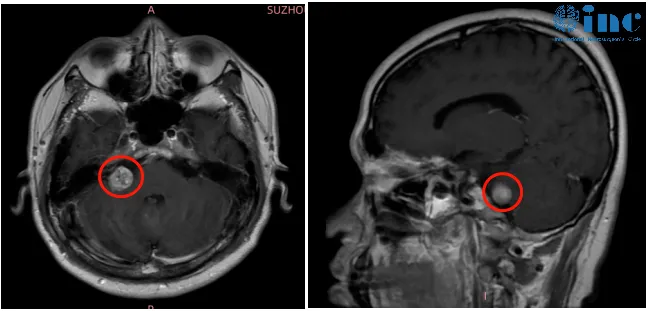

患者虽有偏头痛病史,但此次头痛与既往截然不同,夜间痛醒的情况从未有过。多次就医均无明确结论后,她接受了头部MRI检查,结果令人震惊:左侧桥小脑角区发现31×27×23mm的听神经瘤。回溯病史才想起,自己其实有四年轻度双侧耳鸣史,只因症状轻微一直未加留意,而这枚良性肿瘤,正是那阵反常夜间头痛的真正元凶。

以头痛为首发表现的听神经瘤极为罕见,发生率仅约2%,该患者的症状表现更符合催眠性头痛特征。究其机制,肿瘤位于空间局促的后颅窝,体积增大后压迫周围结构并干扰颅内压调节;夜间平卧时颅内静脉回流减少,进而诱发头痛;肿瘤牵拉硬脑膜、干扰睡眠相关脑区,也进一步加剧了症状。

明确病因后,患者接受了巴教授的精准手术治疗,术后夜间头痛逐渐减轻,六个月后彻底消失。这一病例也提醒公众,听神经瘤症状隐匿易漏诊,若存在耳鸣、听力变化,并伴有顽固性特殊头痛,务必及早排查颅内病变。